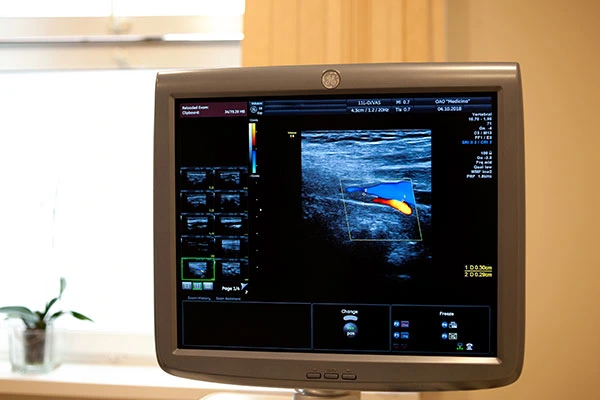

АО «Медицина» (клиника академика Ройтберга) предлагает сделать УЗИ сердца в Москве на инновационном оборудовании от ведущих медицинских брендов в удобное время. Высокая квалификация специалистов клиники, полный комплект диагностического оборудования, возможность проконсультироваться у специалистов других направлений и эффективность применяемых медицинских методик являются несомненными преимуществами обращения в один из ведущих медицинских центров Москвы – многопрофильную клинику АО «Медицина».

Проведение УЗИ в Москве

использование современно оборудования;